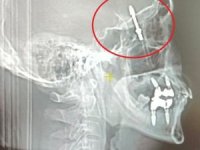

Yaralı öğrencilere olay yerinde ilk müdahalesini yapan sağlık ekipleri gençleri Orhangazi Devlet Hastanesine sevk etti. Polis ekipleri kaza ile ilgili soruşturma başlattı.